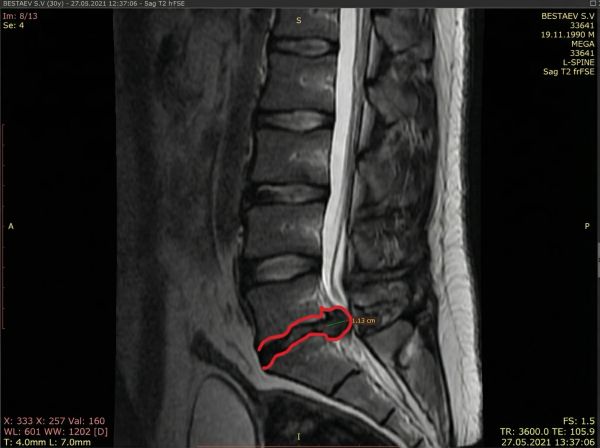

Один из 3170+ успешных случаев

Пациентка, 45 лет. Грыжа секвестрированная, 3.5 сантиметра.

Грыжи нет, остался только рубец.